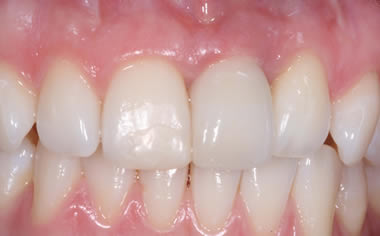

Missing upper front tooth replaced by dental implant and crown